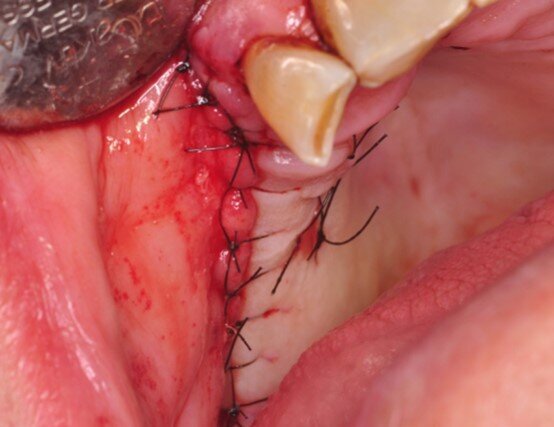

Ryc. 1-3_Stan przed leczeniem: 1. Zdjęcie wewnątrzustne

Ryc. 5_Śródzabiegowo: stan po zamknięciu płata.